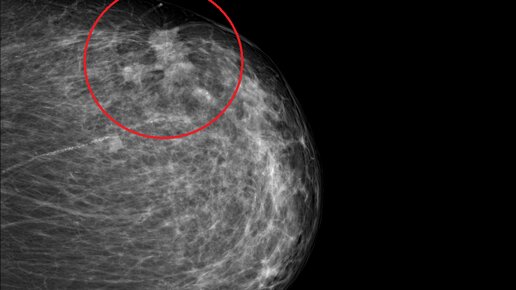

Классические признаки рака молочной железы. Случай из практики.

Пациентка Д., 74 года. Появление уплотнения в левой молочной железе пациентка впервые обнаружила чуть больше года назад, за медицинской помощью не обращалась. Общее самочувствие было нормальным, уплотнение в железе не болело и особо не беспокоило. Около года назад Д. показалось, что она сломала ребро, уперевшись грудью о край стола. Ребро как-будто "хрустнуло", а затем какое-то время болело, но Д. в итоге подумала, что это был ушиб, а не перелом. По данным маммографии левая молочная железа локально...